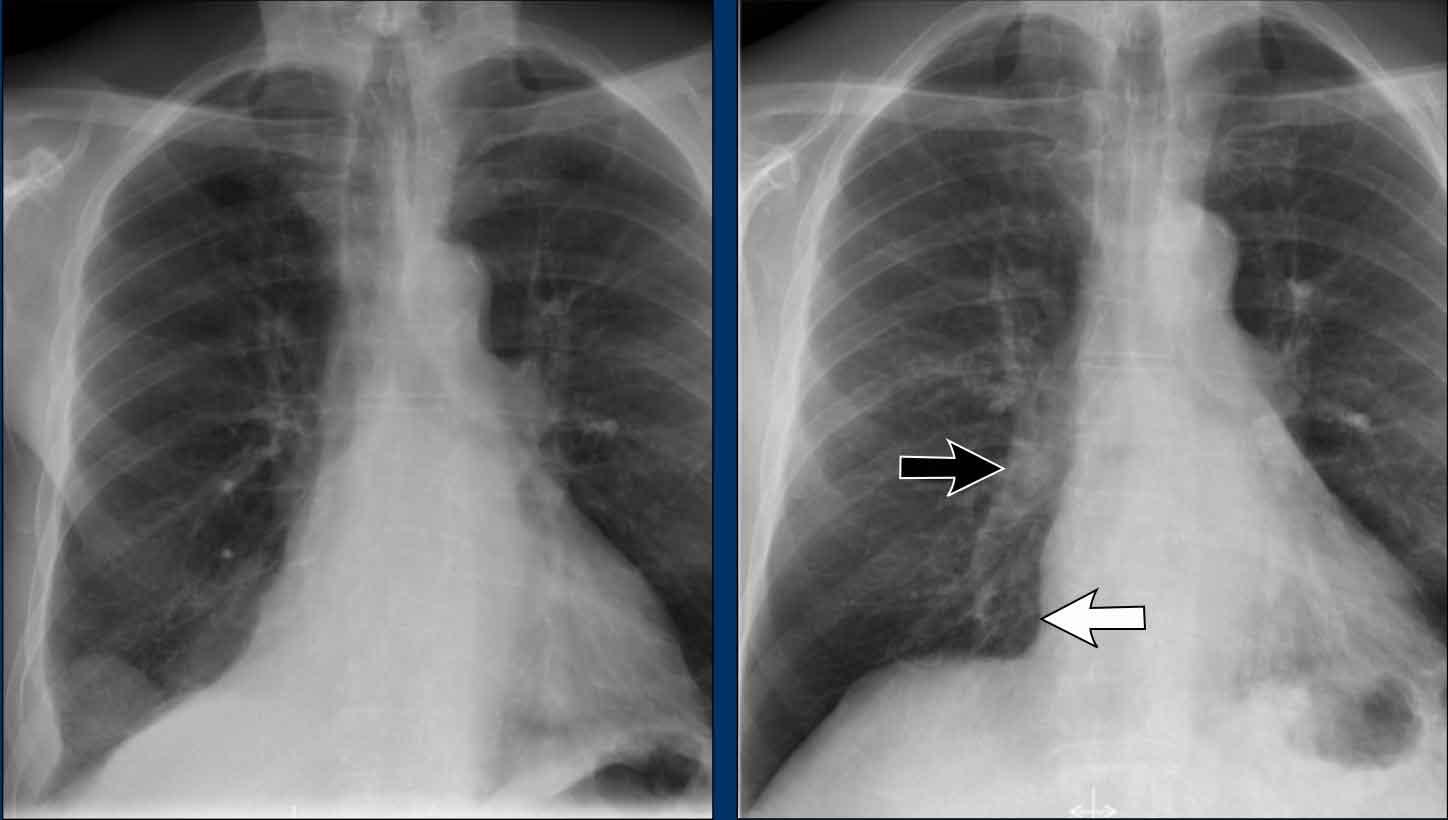

Ví dụ Lâm sàng: Dấu hiệu Kín đáo của Suy tim Sung huyết

Hãy bắt đầu bằng cách xem xét các phim X-quang ngực hiện tại.

Chỉ dựa trên các hình ảnh này, người đọc có thể nghi ngờ suy tim sung huyết (CHF), mặc dù các dấu hiệu còn khá kín đáo.

Bây giờ hãy xem lại phim cũ trước đó…

Việc cuộn qua lại giữa phim hiện tại và phim cũ giúp tăng đáng kể độ tin cậy trong chẩn đoán suy tim sung huyết.

Các dấu hiệu so sánh chính bao gồm:

- Kích thước tim: Tăng nhẹ so với phim trước; tuy nhiên, tim to đã hiện diện từ trước.

- Hệ mạch máu phổi: Cương tụ mạch máu nhẹ gợi ý tăng áp lực tĩnh mạch phổi.

- Hình ảnh mô kẽ: Dấu hiệu kín đáo của phù mô kẽ.

- Tràn dịch màng phổi: Tràn dịch lượng ít hai bên, với thay đổi kín đáo ở bờ dưới-sau của các thùy dưới, gợi ý tích tụ dịch.